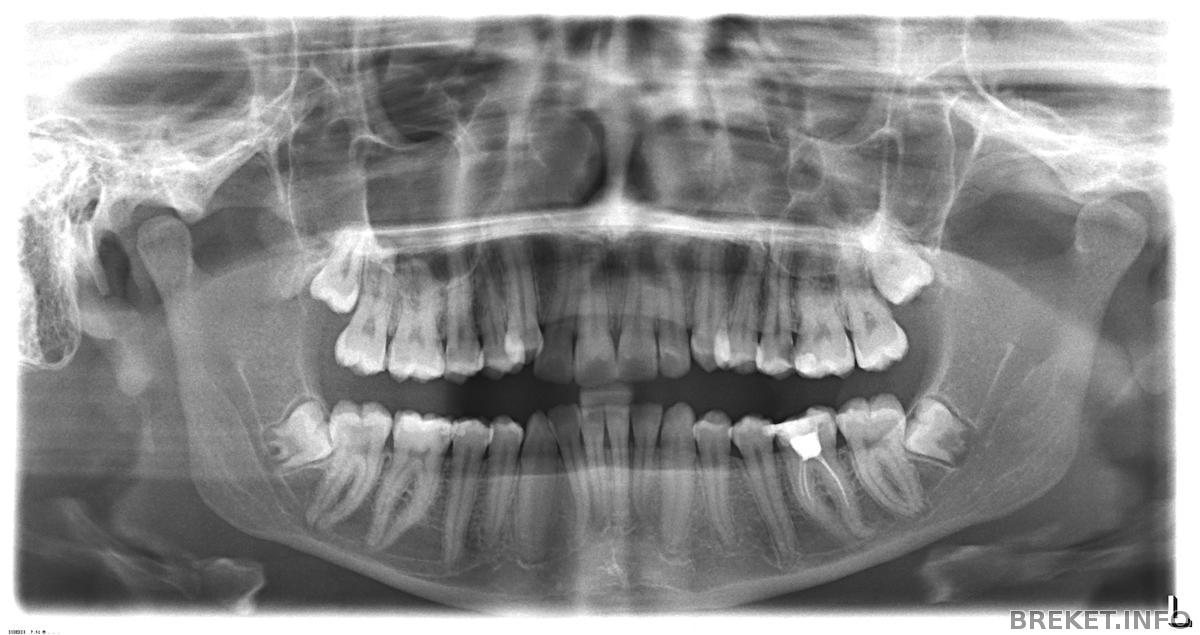

Доктор отправил на круговую панораму, сделала снимок, на нижней челюсти оба зуба мудрости ретенированные, наклонены в сторону остальных зубов, прям-таки расположены горизонтально, а не вертикально, как должны были бы быть. пришла со снимком, врач сказал что их нужно вырезать пока они не начали расти, т.к. если начнут движение искривят остальные зубы. Сказал удалить 2 на НЧ , написал направление к др. доктору в отделение челюстно-лицевой хирургии, говорит удалять будут под общим наркозом!... очень боюсь, именно сам наркоз больше всего пугает, как от него отходят....на консультацию пойду в скором времени.. кому вырезали уже зубы мудрости? расскажите.

правее от восьмерки проходит полосочка. это и есть нерв. это двухмерное изображение. но он большой и находится близко. если бы ортодонту приспичило бы удалять. то я бы делала снимок с другого угла, что бы увидеть как далеко находится нерв. но это всего пару мм.. а это опасно.

зачатки ретинированые - такого не бывает. ретинированые - когда зуб с корнями под десной. а зачатки как на фото.